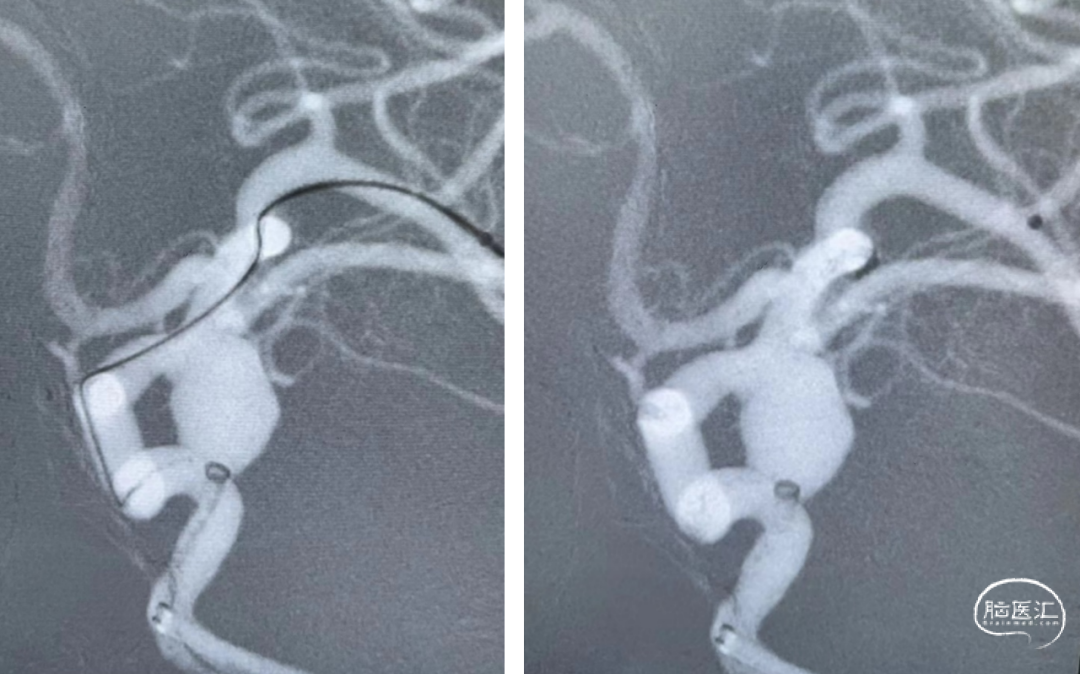

术后即刻造影显示支架完全贴壁,支架内血流通畅,动脉瘤内可见明显造影剂滞留,载瘤动脉通畅,分支血管正常,手术顺利结束。

Nuva®血流导向密网支架是由泰杰伟业公司出品,操作简便,术中释放顺利,其输送系统显影设计新颖,有助于支架循迹释放,良好贴壁;支架通体显影效果优异,术中便于随时观察支架的打开、走行及贴壁情况。